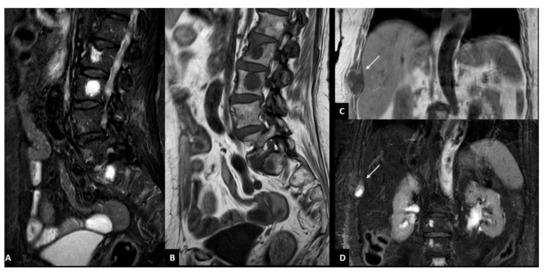

3.3. Radiological Pattern and Lesions’ Distribution

3.4. Standard vs. Short Protocols